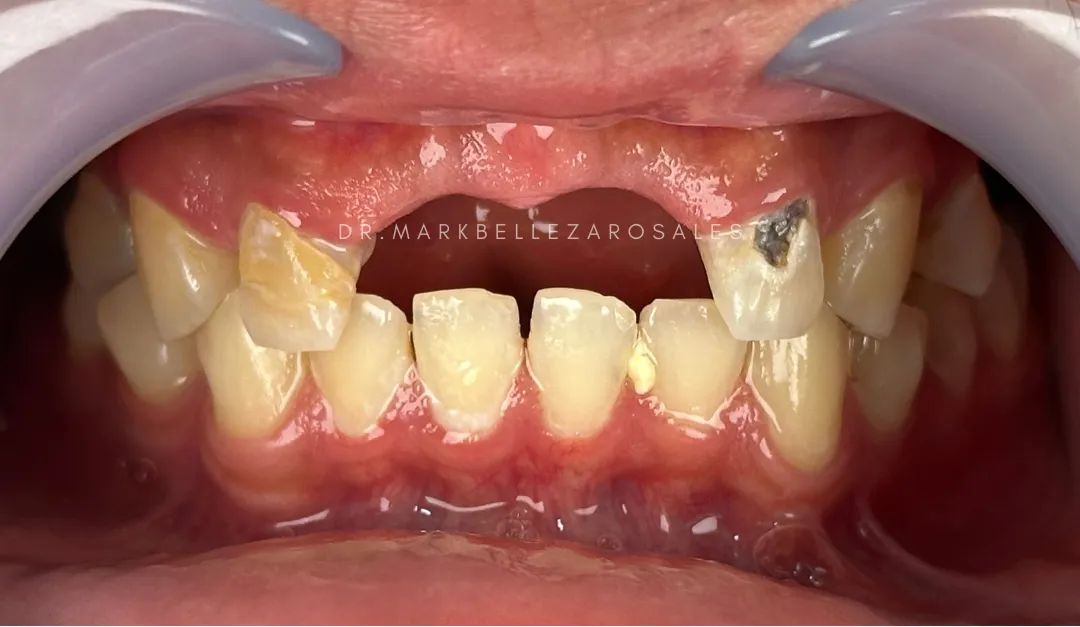

Composite restoration is a tooth-colored dental filling used to repair cavities, chips, or damaged teeth. It blends naturally with the tooth, restores strength and function, and is typically completed in a single dental visit.